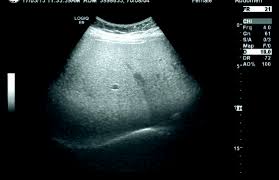

정기적인 건강 검진은 지방간을 조기에 발견하고, 적절한 치료를 받을 수 있는 중요한 방법입니다.

- 혈액 검사: 간 효소 수치, 콜레스테롤, 혈당 등을 체크합니다.

- 초음파 검사: 간의 상태를 초음파를 통해 직접 확인합니다.

- 체성분 분석: 체내 지방 비율을 측정하여 지방간 위험을 평가합니다.

건강 검진 주기

- 연 1회: 최소한 매년 1회 정기적으로 건강 검진을 받습니다.

- 추가 검진: 고위험군(비만, 당뇨, 고혈압 등)은 필요시 추가 검진을 받습니다.